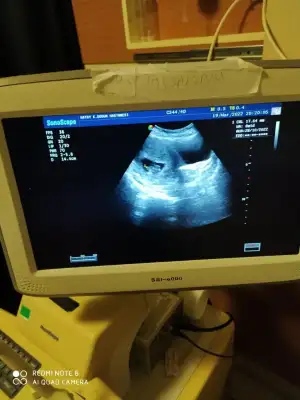

Benim de gecen hafta sonu benzer birsey oldu , sonra ultroson da baktilar hic kanama yok rahimde tertemiz hersey yolunda . sende hersey iyi olacak diye dusun![]()